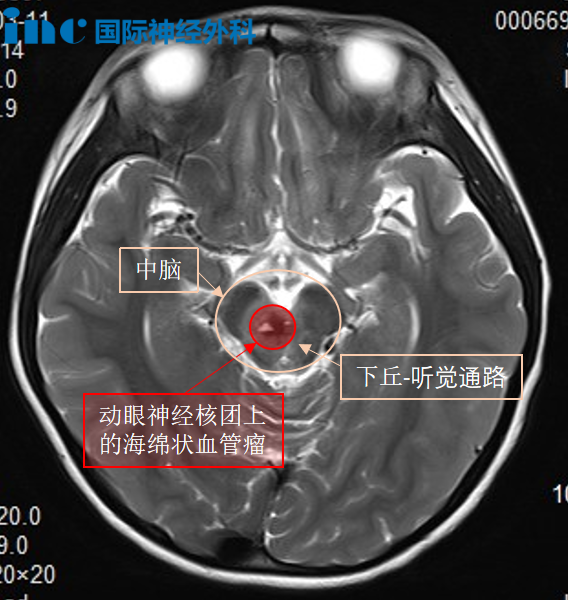

2024年3月,果果感觉眼前模糊,揉了揉眼睛没有在意。仅仅3天后,她突然出现复视、左眼外斜,父母迅速带她前往医院就诊,CT影像却提示:脑干出血,病灶位于中脑偏右侧,怀疑为海绵状血管瘤破裂。

首先,果果的肿瘤位于脑干中脑偏右侧、位置深在、难以进入。脑干仅拇指大小,这么小的区域还划分了桥脑、中脑、延髓三部分,脑干是掌控呼吸、心跳等生命中枢。在如此狭小区域内进行手术,稍有不慎便会损伤功能区。

而且,脑海绵状血管瘤由异常血管团构成,反复出血会侵蚀周围脑组织,形成“含铁血黄素环”,果果的海绵状血管瘤累及动眼神经核——管眼皮、睁眼和眼球活动还有瞳孔,动眼神经核仅有2毫米粗却与肿瘤粘连紧密。